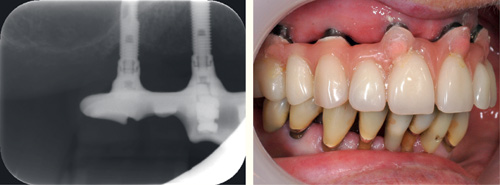

Implantater har gjerne en glatt og blank overflate på områder som er blottlagt i munnhulen, men de består ofte av flere komponenter med små spalter mellom seg. Dette kan gi grobunn for mikroorganismer og dermed forårsake periimplantitt eller manglende osseointegrering (29,35). Implantatene har en betydelig ruere overflate der de skal omsluttes av ben. Redusert benfeste som følge av periimplantitt vil blottlegge den rue overflaten, som vil ha en betydelig høyere adhesjon for orale mikroorganismer og dessuten være mye vanskeligere å rengjøre (figur 6). Dersom en biofilm med ugunstige mikroorganismer får etablere seg på en slik overflate vil den være nærmest umulig å stoppe. Implantatenes direkte kontakt med benvev vil også bety at infeksjoner rundt implantatet lettere kan bli overført direkte i blodbanen (27). Det er ingen bindevevshinne som kan fungere som barriere, slik som det er rundt tenner. Tilgjengelige studier på periimplantitt kan ikke fullt ut forklare hva som er forskjellen eller likheten mellom periimplantitt og periodontitt, men det er mye som tyder på at pasienter som har eller har hatt alvorlig periodontitt også er mer utsatt for periimplantitt (36). Mikrofloraen rundt et implantat med sunt og friskt støtteapparat tilsvarer mikrofloraen rundt tenner med frisk gingiva (37). Mikrofloraen ved periimplantitt er tilsvarende som periodontitt, men ofte med større innslag av sopp og tilstedeværelse av flere bakteriearter enn det som vanligvis observeres ved periodontitt (37). Dette skyldes trolig at metallet og overflaten på implantatet påvirker biofilmen som dannes der. Det er ennå usikkert om dette vil påvirke behandlingen av periimplantitt.

Figur 6. Implantat i regio 16 med blottlagte skrueriller med ru overflate som følge av tidligere periimplantitt. Foto: M. Øilo.